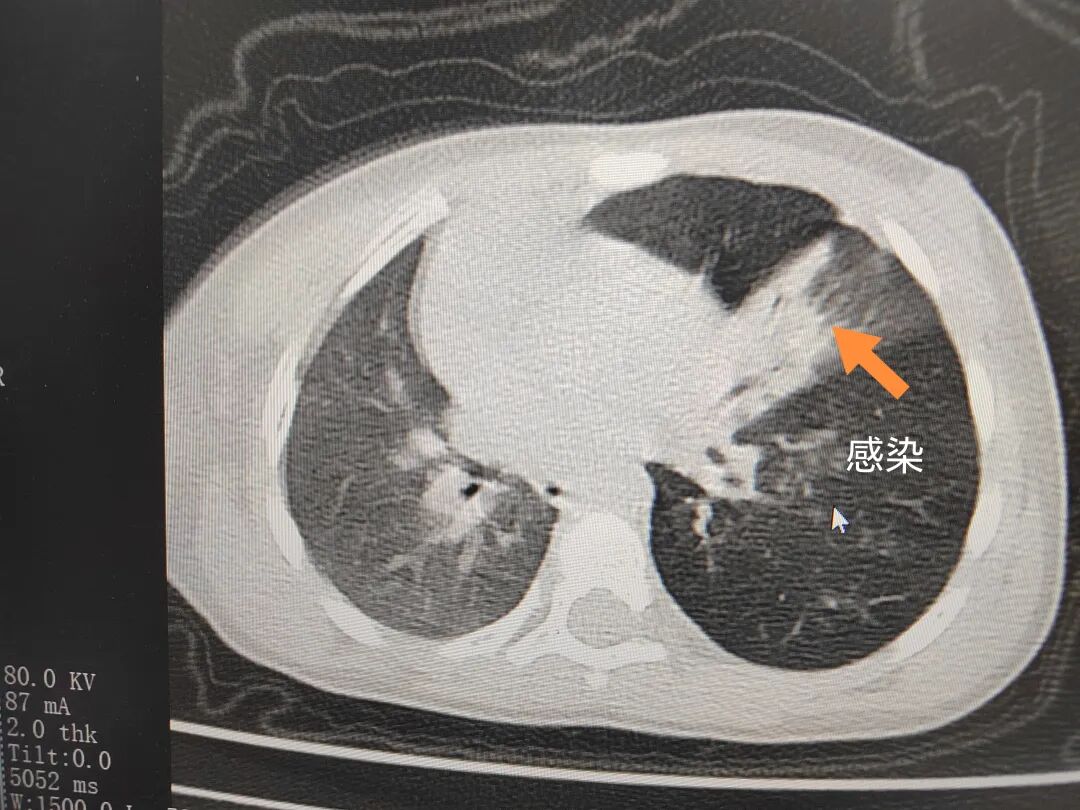

三天后(11月13日),趙寶出現(xiàn)高熱、咳喘加重,家長著急了,再次帶他來到醫(yī)院。CT檢查顯示左肺過度充氣,左肺上下葉支氣管主干見不規(guī)則高密度影,左肺上葉可見大片狀密度增高影,縱隔窗實(shí)變,提示為“左側(cè)支氣管內(nèi)異物并繼發(fā)性改變,左肺上葉舌段肺膨脹不全”。

市二院小兒呼吸內(nèi)科副主任楊亞娟介紹,異物誤入氣道可能導(dǎo)致氣道阻塞,嚴(yán)重時可引發(fā)窒息,甚至危及生命。若異物進(jìn)入支氣管,造成不完全堵塞,可引起阻塞性肺氣腫;如完全堵塞支氣管,則可能導(dǎo)致肺組織萎縮,形成肺不張。此外,若異物存留時間較長,或?yàn)橹参镄援愇?,容易合并?xì)菌感染,產(chǎn)生膿性分泌物,進(jìn)而發(fā)展為肺炎。她強(qiáng)調(diào),盡早診斷并取出異物,是減少并發(fā)癥、降低病死率的關(guān)鍵。